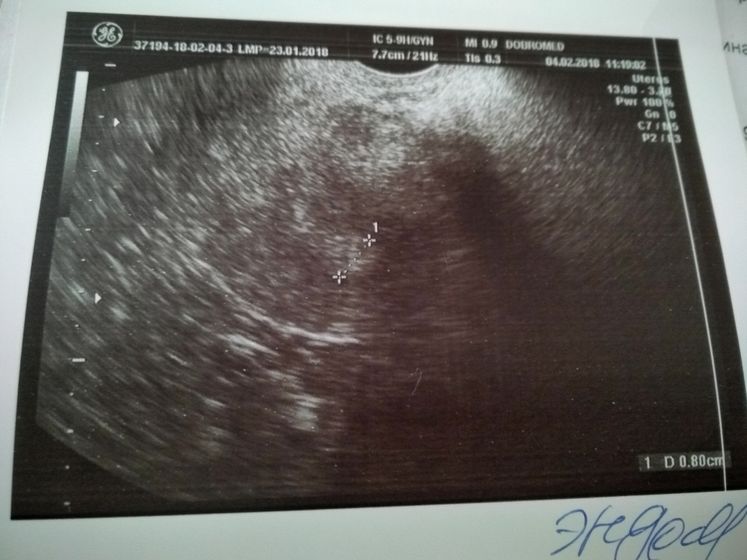

Поехали сегодня в пургу и вьюгу на УЗИ в Добромед(не в восторге) Сделали узи, рассказала что и как врачу, при осмотре было желтое тело, но как я поняла, не совсем то что нужно. В остальном все хорошо, матка, яичники все в норме. Критичного ни чего нет. Послали на ХГЧ завтра за результатом. Если есть, кто разбирается в заключении и в узи, буду рада информации. Тест все еще показывает //

Ну срок ещё маленький скорее всего, поэтому не увидели

Значит есть шанс?